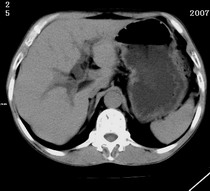

以下是引用zjzjr在2007-9-15 22:24:00的发言:[br]胰头钩突略饱满,肝内外胆管略扩张,胆囊积水.建议增强扫描.

以下是引用代课学生在2007-9-16 10:20:00的发言:[br]胆总管中段以上胆管均示扩张,考虑胆总管下段/胰头部病变,建议增强或micp检查。